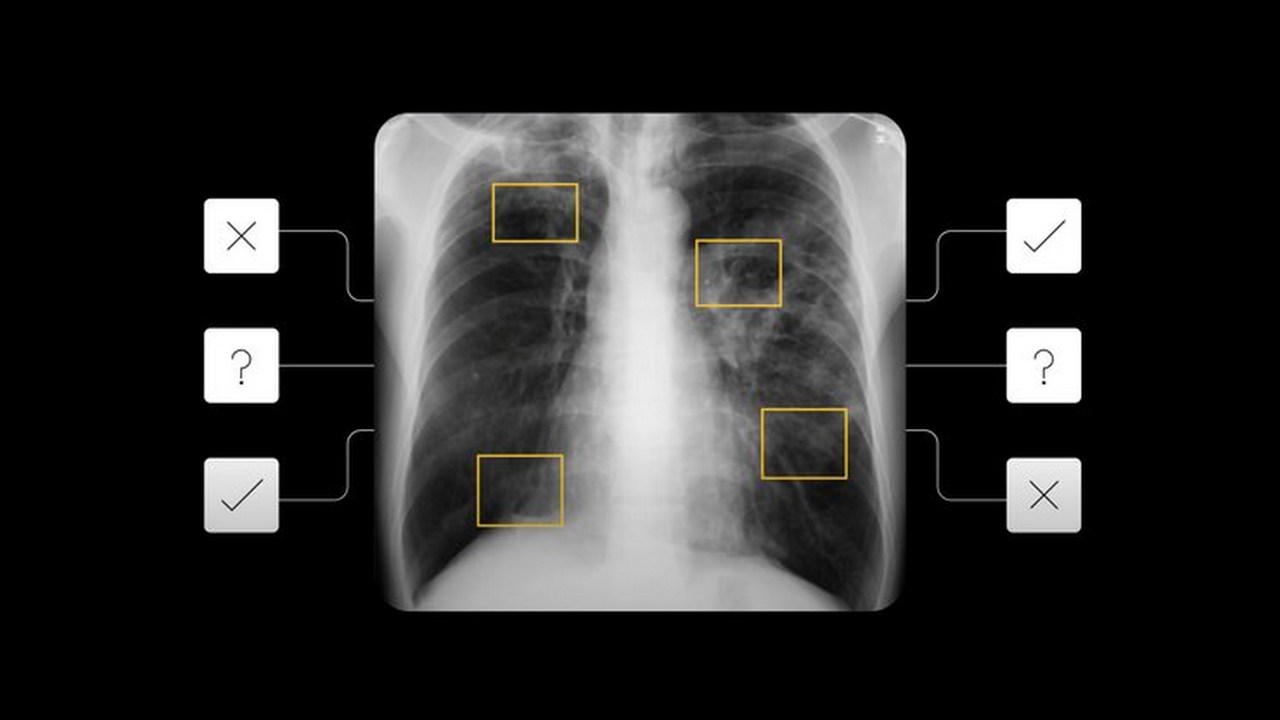

published new research in the area of Artificial Intelligence (AI) which can be used for tuberculosis (TB) screening. As per a blog post, the researchers at Google have developed AI research that builds on the existing medical imaging work and helps patients with Tuberculosis be identified for consecutive tests. The company confirms that this diagnostic procedure is a preliminary test and can save up to 80 percent of the cost of an expensive diagnostic test per TB patient. [caption id=“attachment_9635371” align=“alignnone” width=“1280”] The deep learning system provides any number between 0 and 1, indicating the severity of tuberculosis in the patients. Image: Google[/caption] The previous research which detected nodules or fractures in chest X-rays or collapsed lungs was used to build the latest AI tool. In order to ensure that the AI tool is effective on a wide range of races, Google trained the model using de-identified data from nine countries. It was then tested on cases from five countries. In their study, the Google AI researchers have found that on the basis of the chest X-ray, the deep learning system can identify patients who are likely to have active TB. It provides any number between 0 and 1, indicating the severity of tuberculosis in the patients. Google’s AI tool was able to accurately detect the cases of TB. The blog also states that the detection rates of false-negative and false-positive cases were similar to 14 radiologists. One of the highlights of this latest AI tool is that it is able to maintain detection accuracy even while examining HIV patients. Generally, it is difficult to screen TB in HIV patients as their chest X-rays may differ from those of other TB patients. For the implementation of this AI tool, the tech giant says that there needs to be agreement on the risk level which makes a person eligible for additional testing. Also read: